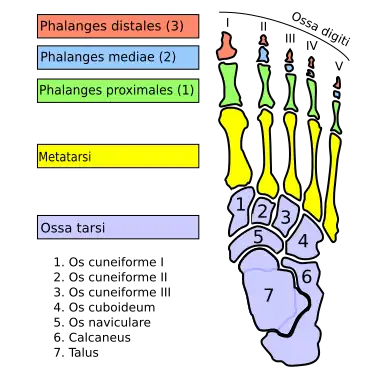

Das Sprungbein oder Rollbein, älter auch Fesselknochen,[1][2] lateinisch Talus, veraltet auch Astragalus und Astragal, ist ein kurzer Knochen und Bestandteil der Fußwurzel und des Sprunggelenkes. Es liegt zwischen Knöchelgabel (Malleolengabel) und Fersenbein (Calcaneus) und verbindet den Fuß mit dem Bein.

Der Talus besteht aus dem Körper (Corpus tali), dem Hals (Collum tali) und dem Sprungbeinkopf (Caput tali).

Auf dem Sprungbeinkopf befindet sich die Gelenkfläche für das Kahnbein (Naviculare). Diese Gelenkfläche wird als Facies articularis navicularis bezeichnet. Hier liegt der kugelförmige Kopf in der konkaven Gelenkfläche des Kahnbeines, wodurch das Talonavikular-Gelenk gebildet wird. Die Gelenkfläche ist Bestandteil der vorderen Abteilung des unteren Sprunggelenkes (USG).[3]